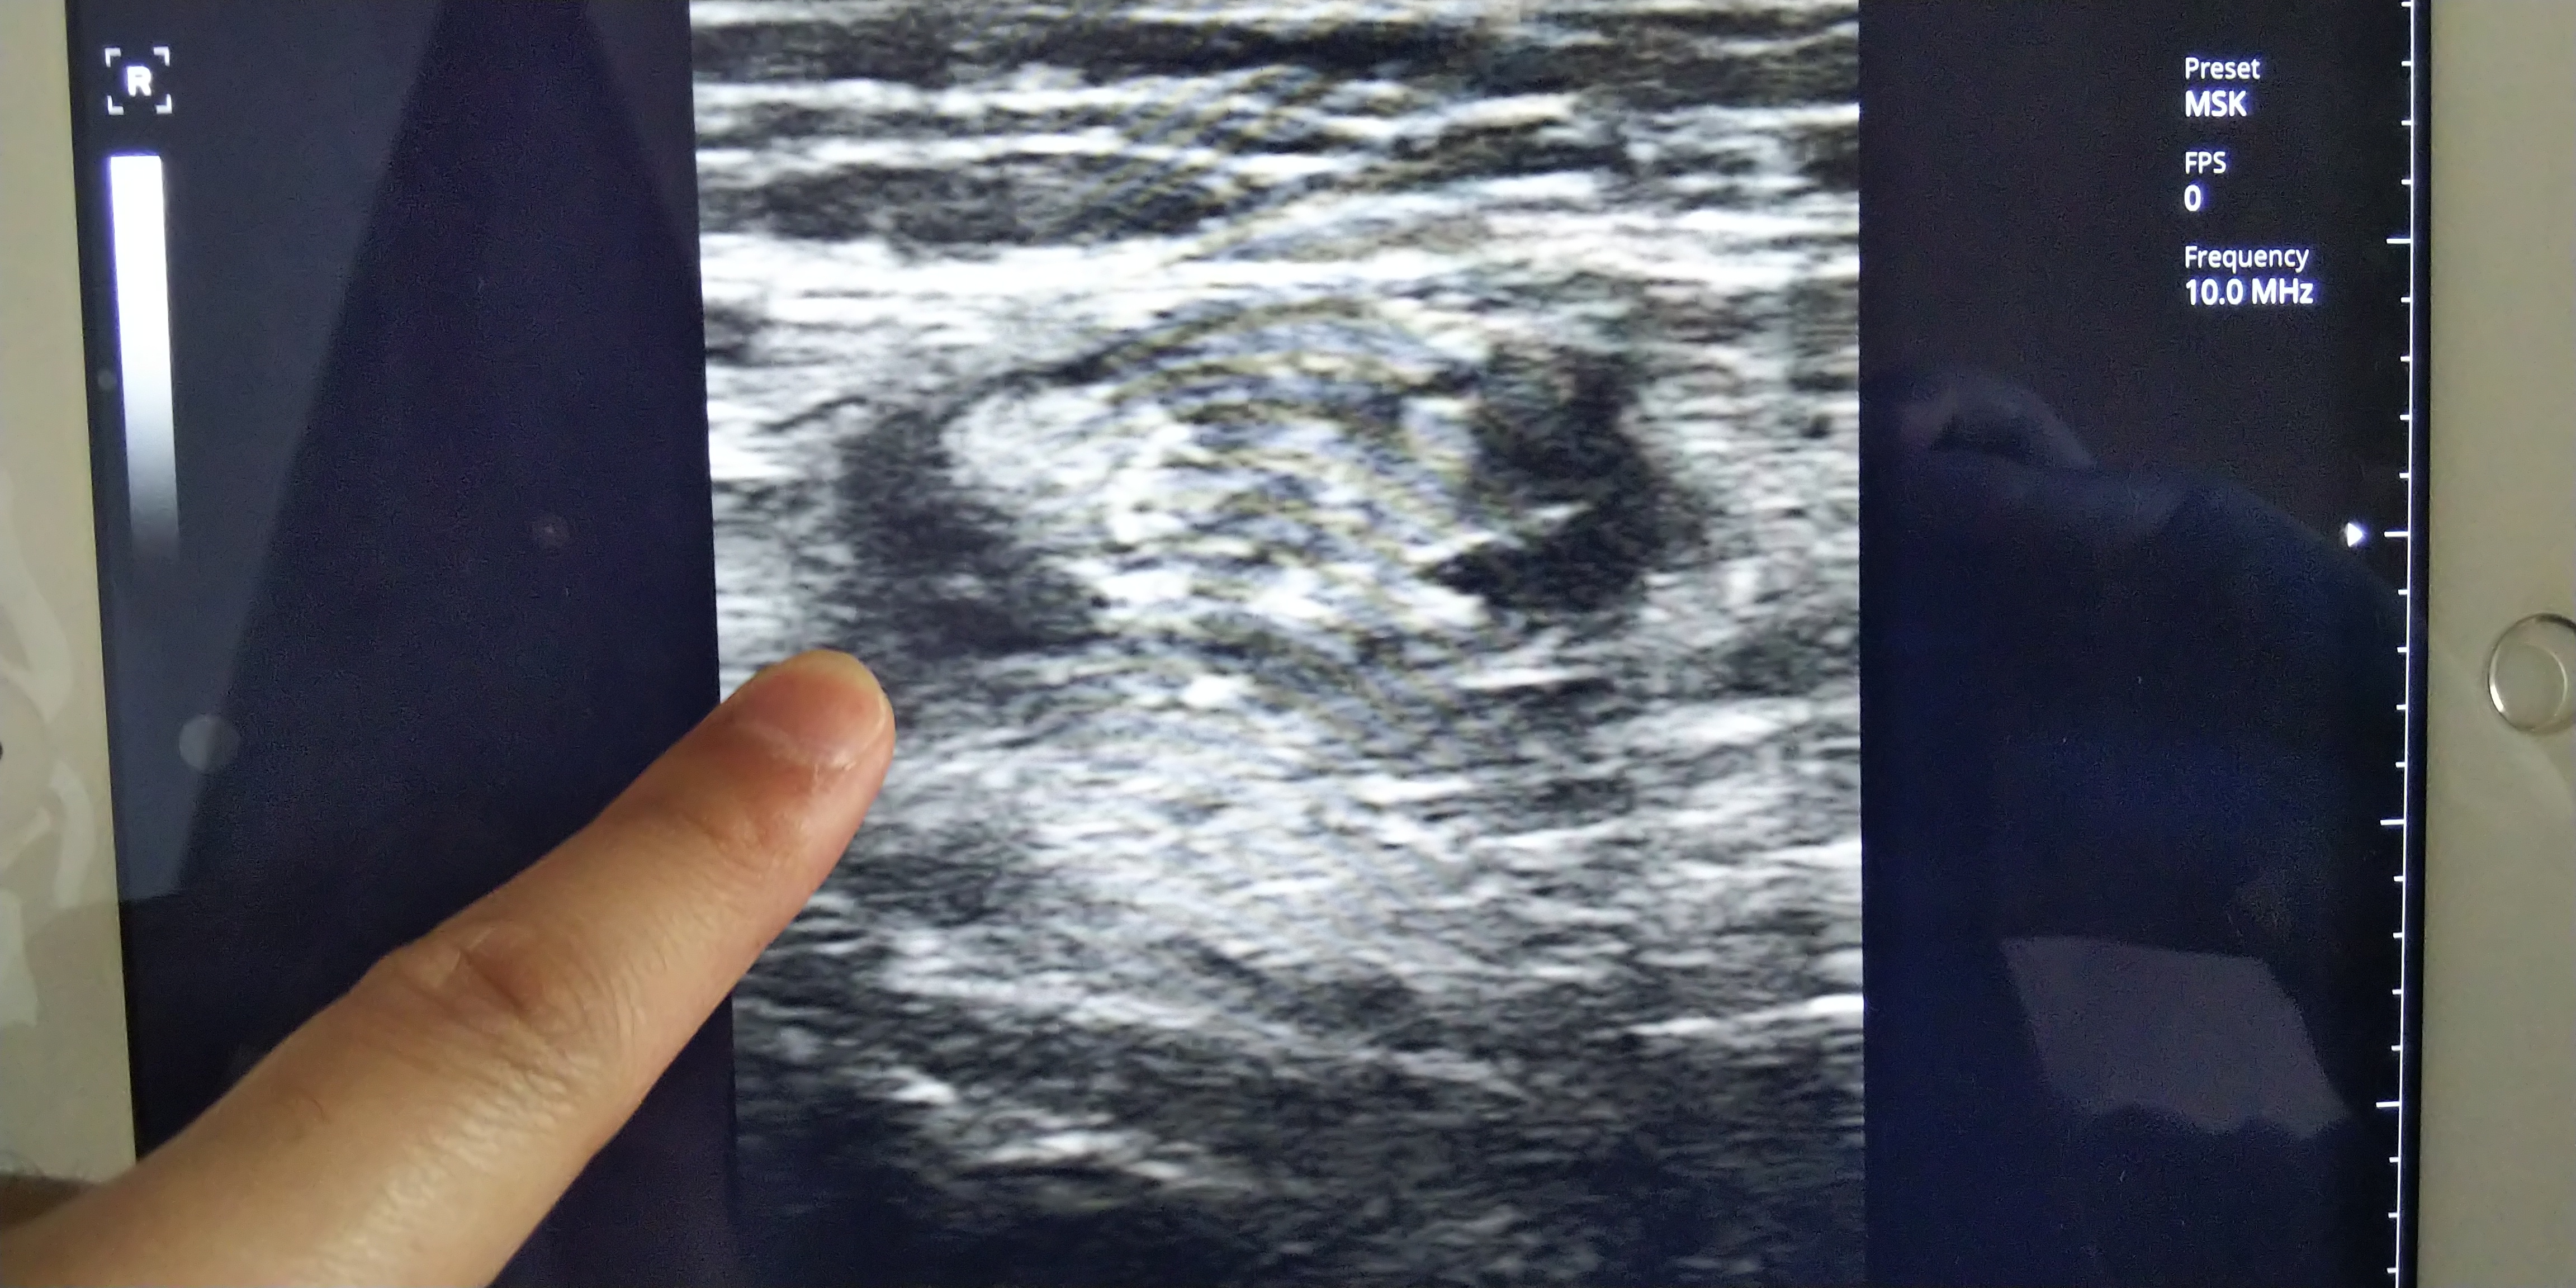

問診・視診・触診をし肉離れの疑いがあったためエコー観察をした。

肉離れのⅡ度損傷を確認。

肉離れはレントゲンでは確認できませんが、エコーではハッキリと確認できます。